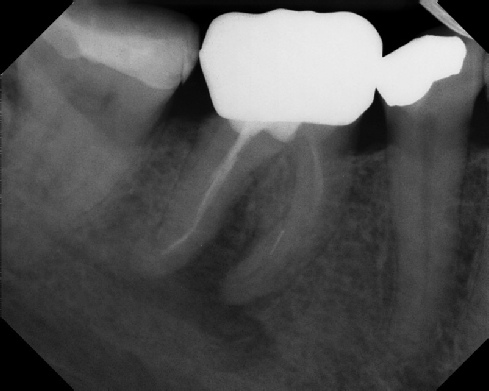

COMPLICATED ANATOMY LARGE LESIONS CALCIFIED CANALS PERFORATION / RESORPTION SEPARATED INSTRUMENTS SURGICAL CASES RETREATMENT / pOST REMOVAL OPEN APICES ACCESS THRU CROWNS Root Canal Case Portfolio

Pre-op Post-op 1 Post-op 2